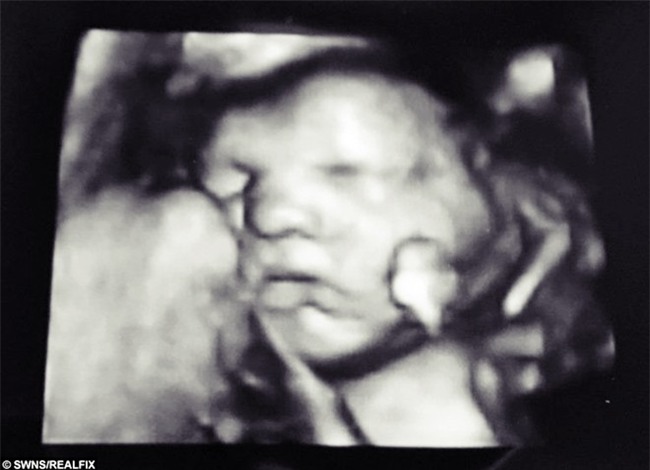

Ở tuần thứ 32, Laura Brown đi khám thai và chụp ảnh 4D để biết tình trạng phát triển hiện tại của em bé. Trong khi y tá thăm khám cô có hỏi vui hai vợ chồng đã có ý định đặt tên cho em bé chưa. Alex rất phấn khởi bật ra cái tên "Frankie" thì ngay lập tức, điều kỳ diệu đã xảy ra.

Bàn tay của em bé bỗng dưng nhúc nhích, ngón trỏ và ngón giữa của bé đặt lên môi tạo thành một hình chữ V hoàn hảo.

Ngón tay em bé bất ngờ dịch chuyển tạo thành chữ V trong tích tắc.